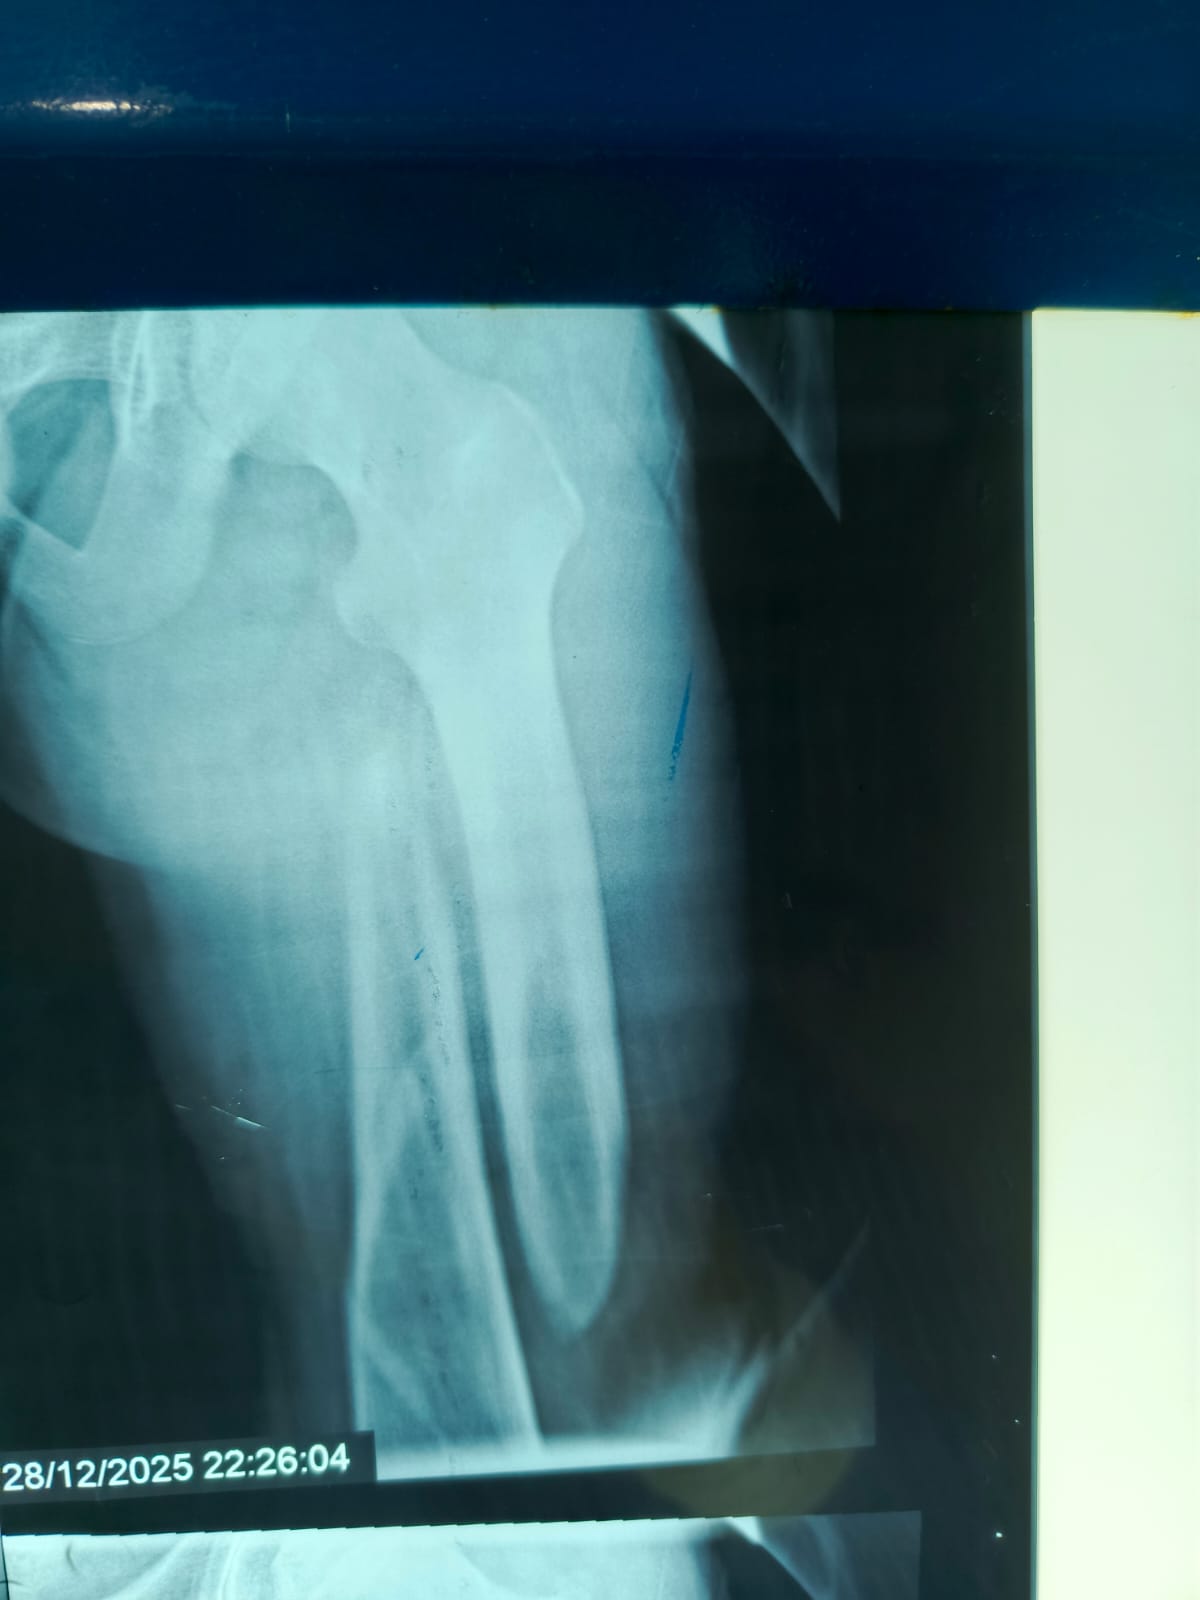

مستشفى مغاغة العام ينقذ شاباً مصاباً بكسر معقد في الفخذ بعد حادث مروري

حقق الفريق الطبي بمستشفى مغاغة العام بمحافظة المنيا إنجازاً طبياً جديداً، بعدما نجح في إنقاذ شاب يبلغ من العمر 16 عاماً، وصل إلى المستشفى إثر حادث مروري عنيف أسفر عن كسر مفتت متعدد المواضع بعظمة الفخذ الأيسر، في تدخل عكس سرعة الاستجابة وكفاءة التعامل مع الحالات الطارئة.

تدخل جراحي سريع بتقنيات حديثة

استنفرت أطقم الطوارئ جهودها فور وصول المصاب، واتخذ الفريق الطبي قراراً عاجلاً بإجراء جراحة المسمار النخاعي التشابكي دون فتح موضع الكسر، ما ساهم في تقليل المضاعفات وتسريع وتيرة العلاج.

أنهى الفريق الجراحي العملية خلال ساعتين ونصف، وخرج الشاب من غرفة العمليات في حالة مستقرة، وفق معايير طبية حديثة تعتمد على التدخل محدود الجروح، وتقليل فقدان الدم، وخفض فرص العدوى، مع تسريع معدلات التئام العظام مقارنة بالأساليب التقليدية.